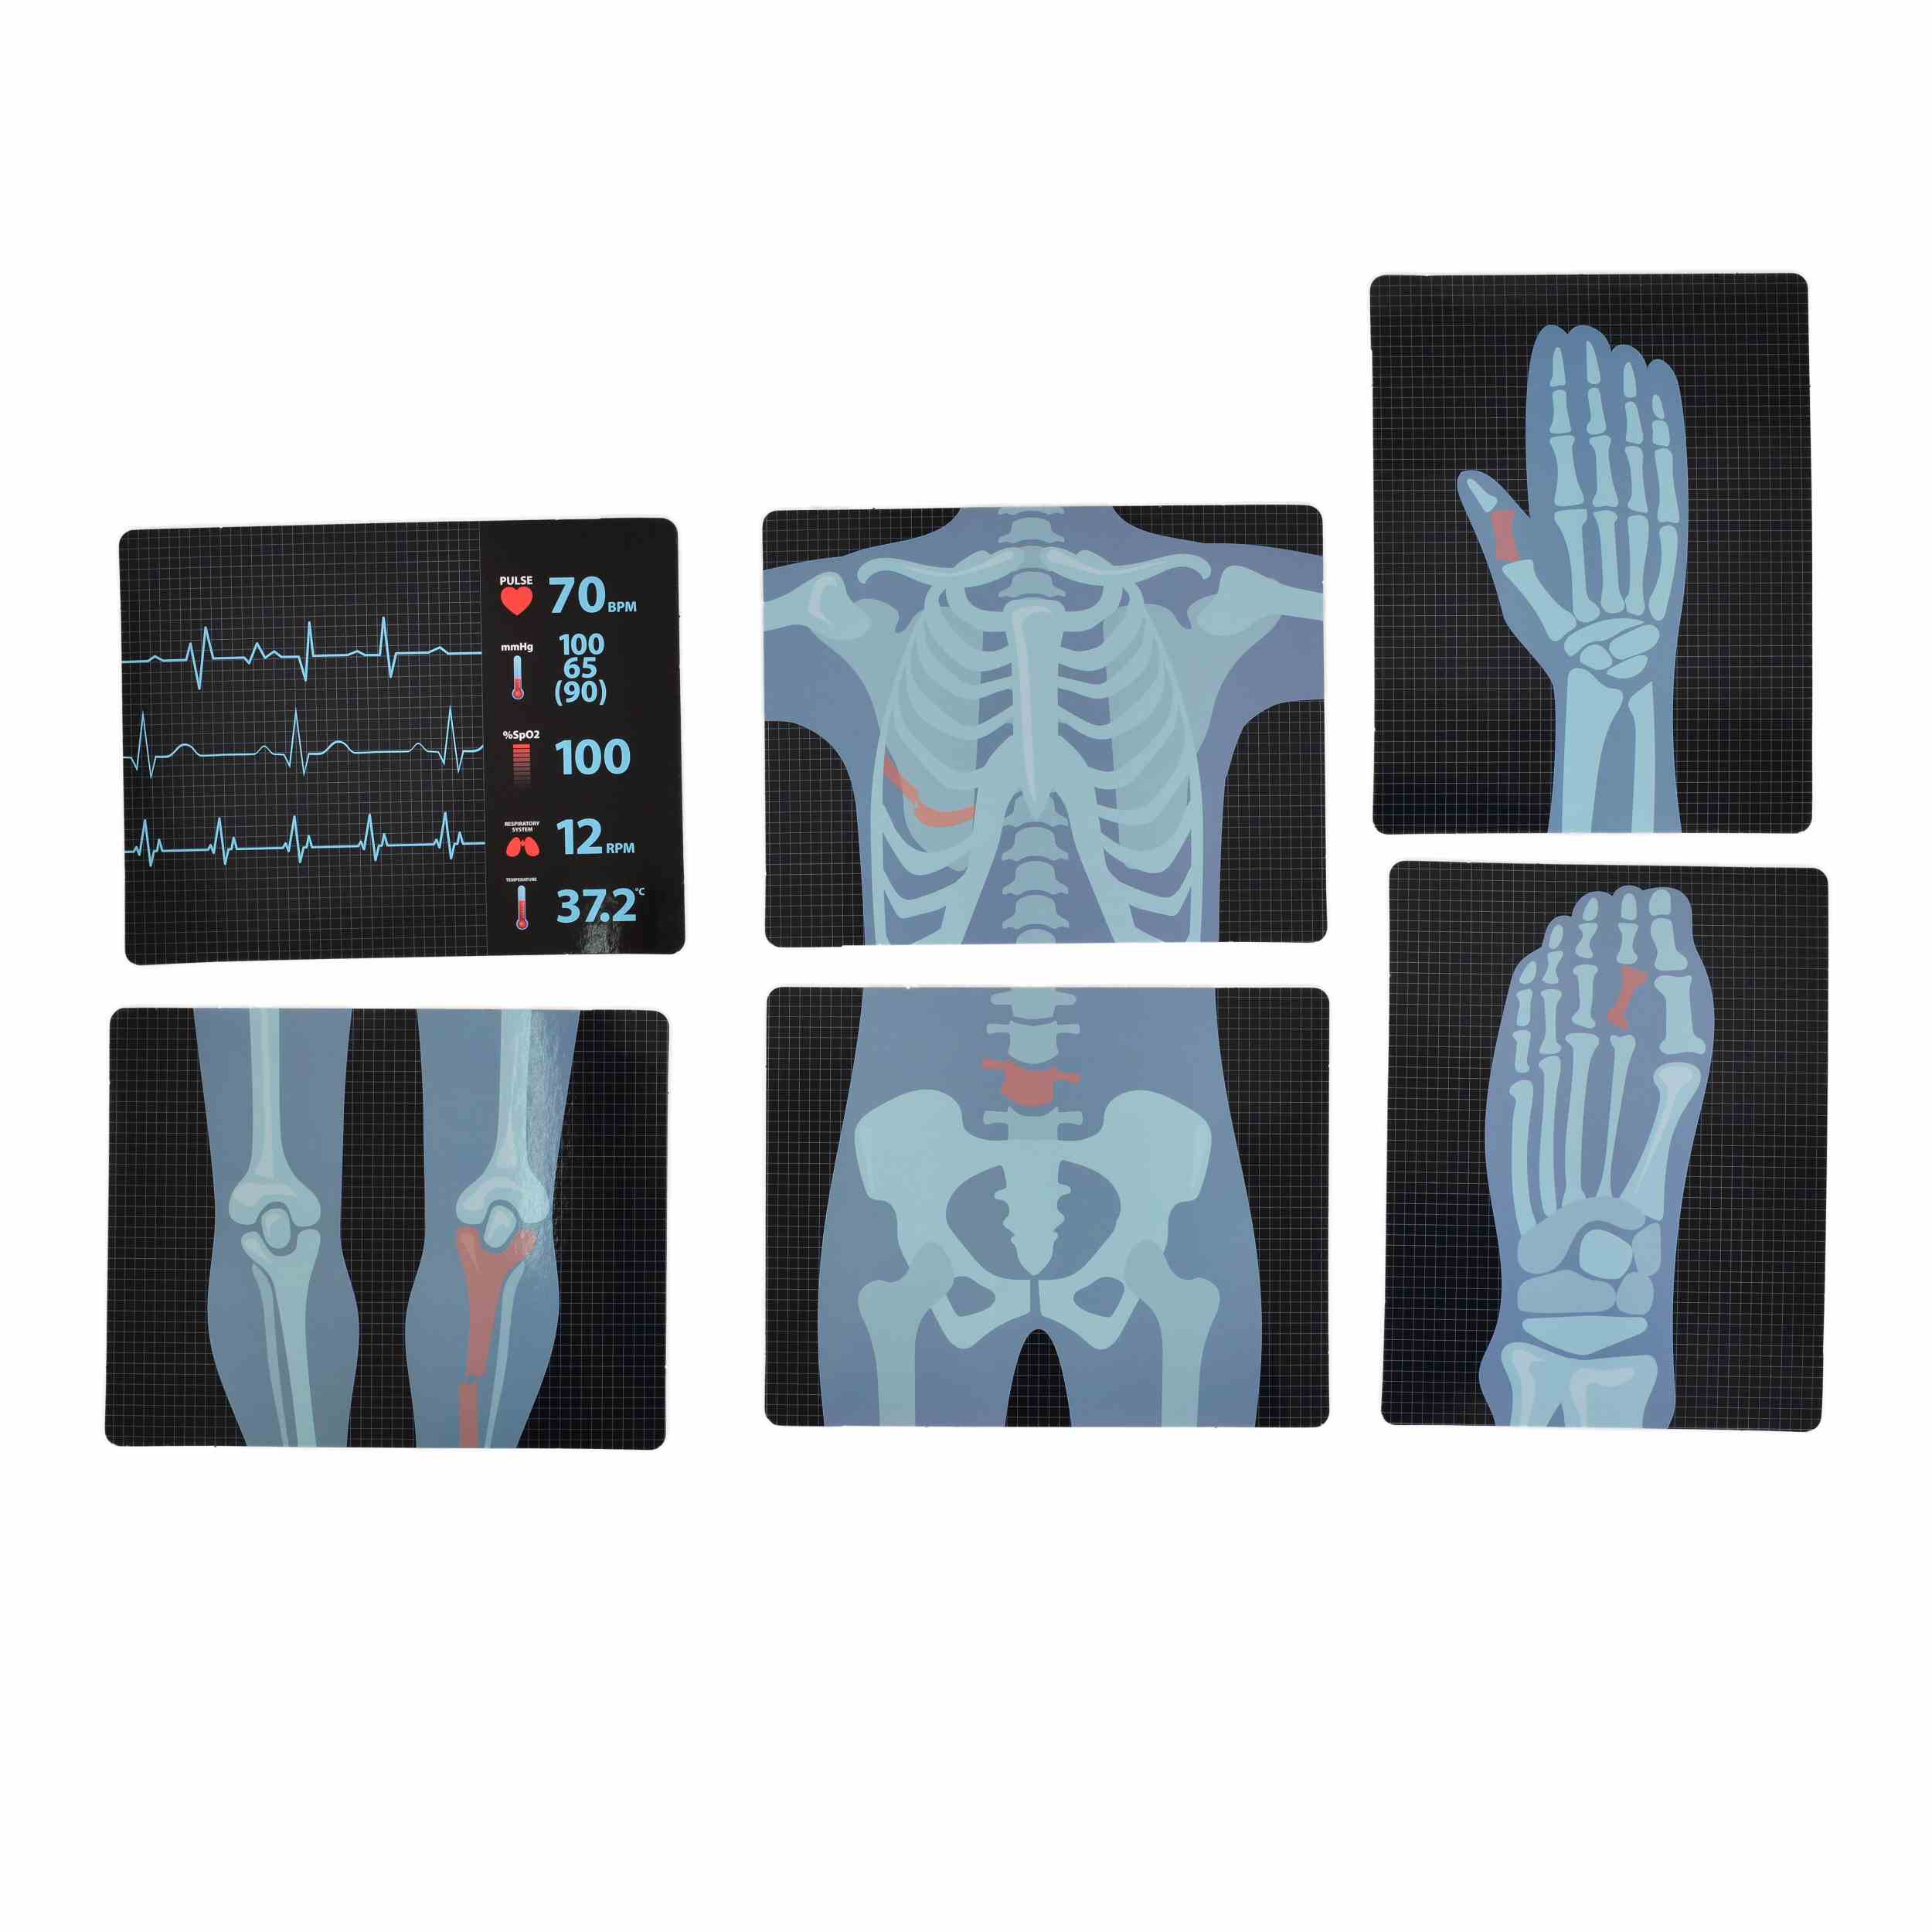

Електрокардиограф: Разполага с бутон за включване/изключване (ON/OFF), бутон за мелодии, бутон за звуци и бутон за образователни мелодии. Работи с 2 x 1.5V AG13/LR44 клетъчни батерии (включени в комплекта).